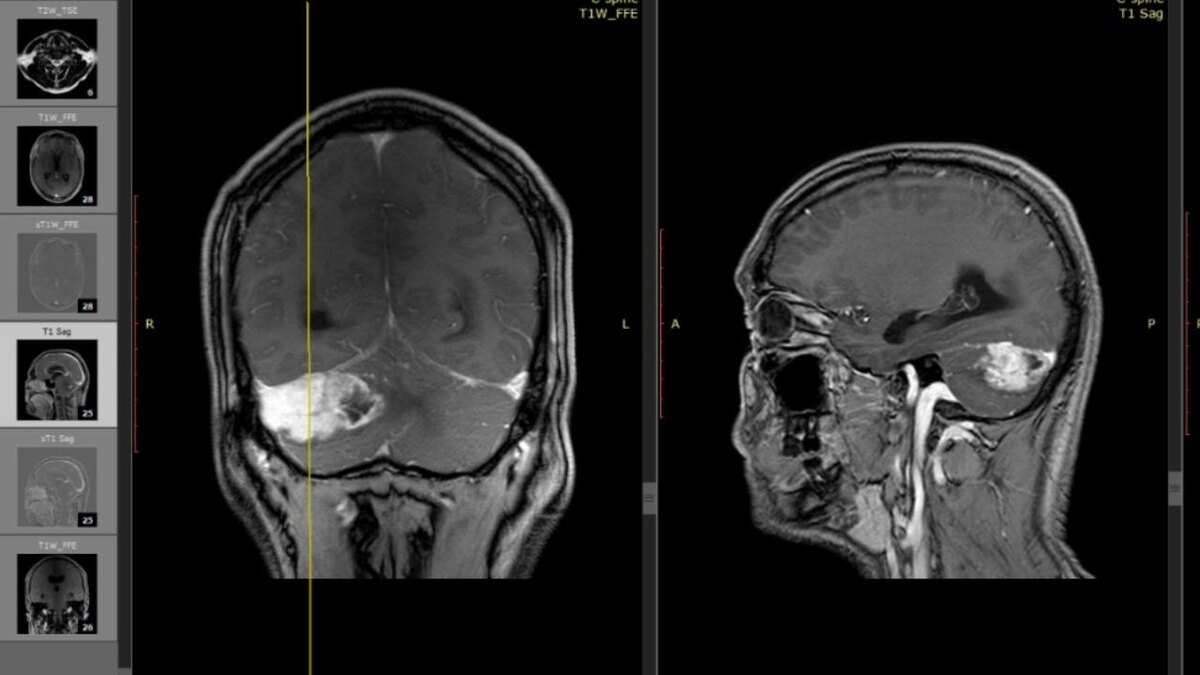

По информации пресс-службы Новосибирской областной клинической больницы, магнитно-резонансная томография выявила у пациента новообразование размером с куриное яйцо.

Опухоль требовала немедленного хирургического вмешательства, так как могла заблокировать ликворопроводящие пути.